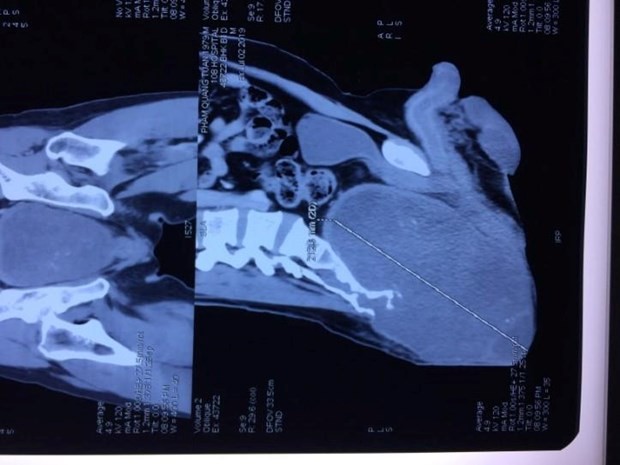

Phim chụp khối u của bệnh nhân. (Ảnh: PV/Vietnam+)

Ngày 7/10, theo thông tin từ Bệnh viện Trung ương Quân đội 108, các bác sỹ của bệnh viện đã phẫu thuật thành công, cắt khối u khổng lồ vùng mông, với kích thước 15x14x20cm cho một bệnh nhân.

Qua thăm khám, các bác sỹ khoa Chấn thương Chỉnh hình Cột sống chẩn đoán bệnh nhân mắc bệnh u nguyên sống (Chordoma) khổng lồ vùng cùng cụt, khối u phát triển ra cả phía trước xương cùng, đè đẩy rất nhiều vào bóng trực tràng và bàng quang.

Khối u gây biến dạng lớn, khiến bệnh nhân không ngồi thẳng và nằm ngửa được từ một năm nay.

Thạc sỹ Nguyễn Duy Thụy cho biết đây là trường hợp u nguyên sống xương cùng cụt thứ 10 tại khoa Chấn thương-Chỉnh hình Cột sống từ năm 2008 đến nay. Điều đặc biệt là khối u của bệnh nhân trên có kích thước khổng lồ, u lớn nhất trong các bệnh nhân đã điều trị tại khoa.